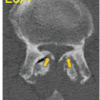

Case Report: A 65 year old woman presented with anterior knee pain and inability to flex her knee more than 90° since 1 year. Clinical examination and imaging studies revealed a nodular calcific mass in the anterior portion of the knee i.e. patella. Following excision, histopathology confirmed the diagnosis of extra-osseous osteochondroma-like soft tissue mass, with no recurrence in 36 weeks.

Clinical examination shows Firm nodular mass was present in the anterior part of the knee, extending superiorly, inferiorly, medially and laterally as well. There was no joint line tenderness present Range of motion was Flexion was restricted to 90 degree and full extension was possible. Neurovascular examination was normal Serology was normal. Surgical excision of mass was done. Intraoperatively Mass involves complete patella but femoral condyle, tibial condyle and patellar tendon was not involved. Post operatively Recovery was uneventful and patient returned to activity of daily living after 2 weeks. She regained 110 degree of flexion Histopathological examination reveals Osteochondroma features with no evidence of malignancy After 6 months patient was asymptomatic and there was no clinical and radiological evidence of reoccurrence.